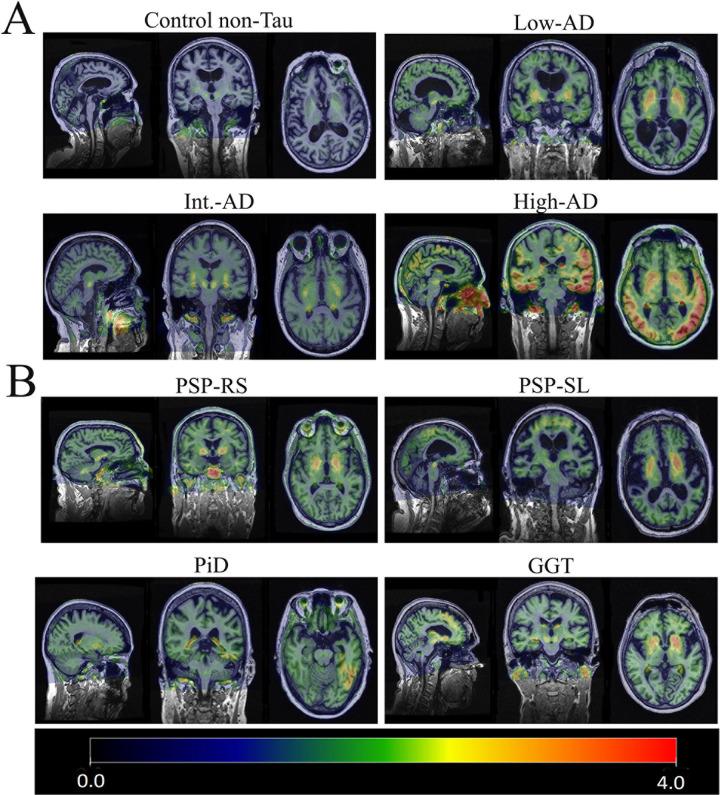

Flortaucipir (FTP) PET is a key imaging technique to evaluate tau burden indirectly. However, it appears to have greater utility for 3R+4R tau found in Alzheimer's disease (AD), compared to other non-AD tauopathies. The purpose of this study is to determine how flortaucipir uptake links to neuropathologically determined tau burden in AD and non-AD tauopathies. We identified nine individuals who had undergone antemortem tau-PET and postmortem neuropathological analyses. The cohort included three patients with low, moderate, and high AD neuropathologic changes (ADNC), five patients with a non-AD tauopathy (one Pick's disease, three progressive supranuclear palsies, and one globular glial tauopathy), and one control without ADNC. We compared regional flortaucipir PET uptake with tau burden using an anti-AT8 antibody. There was a very good correlation between flortaucipir uptake and tau burden in those with ADNC although, in one ADNC patient, flortaucipir uptake and tau burden did not match due to the presence of argyrophilic grains disease. Non-AD patients showed lower flortaucipir uptake globally compared to ADNC patients. In the non-AD patients, some regional associations between flortaucipir uptake and histopathological tau burden were observed. Flortaucipir uptake is strongly linked to underlying tau burden in patients with ADNC but there are instances where they do not match. On-the-other hand, flortaucipir has a limited capacity to represent histopathological tau burden in non-AD patients although there are instances where regional uptake correlates with regional tau burden. There is a definite need for the development of future generations of tau-PET ligands that can detect non-AD tau.

氟脱氧酪氨酸(FTP)正电子发射断层扫描(PET)是一种间接评估 tau 负担的关键成像技术。然而,与其他非 AD tau 病相比,它似乎对阿尔茨海默病(AD)中发现的 3R+4R tau 更有用。本研究旨在确定氟脱氧酪氨酸摄取与 AD 和非 AD tau 病中神经病理学确定的 tau 负担之间的联系。我们确定了 9 名接受过 tau-PET 正电子发射断层扫描和死后神经病理学分析的个体。该队列包括 3 名 AD 神经病理学变化(ADNC)程度低、中、高的患者,5 名非 AD tau 病患者(1 名 Pick 病、3 名进行性核上性麻痹和 1 名球状神经胶质 tau 病),以及 1 名无 ADNC 的对照者。我们使用抗 AT8 抗体比较了区域氟脱氧酪氨酸 PET 摄取与 tau 负担。尽管在一名 ADNC 患者中,由于存在嗜银颗粒病,氟脱氧酪氨酸摄取和 tau 负担不匹配,但在有 ADNC 的患者中,氟脱氧酪氨酸摄取与 tau 负担之间存在很好的相关性。与 ADNC 患者相比,非 AD 患者的氟脱氧酪氨酸摄取总体上较低。在非 AD 患者中,观察到氟脱氧酪氨酸摄取与组织病理学 tau 负担之间存在一些区域相关性。在 ADNC 患者中,氟脱氧酪氨酸摄取与 tau 负担密切相关,但有些情况下两者并不匹配。另一方面,氟脱氧酪氨酸在非 AD 患者中检测 tau 的能力有限,但在某些情况下,区域摄取与区域 tau 负担相关。因此,迫切需要开发能够检测非 AD tau 的下一代 tau-PET 配体。